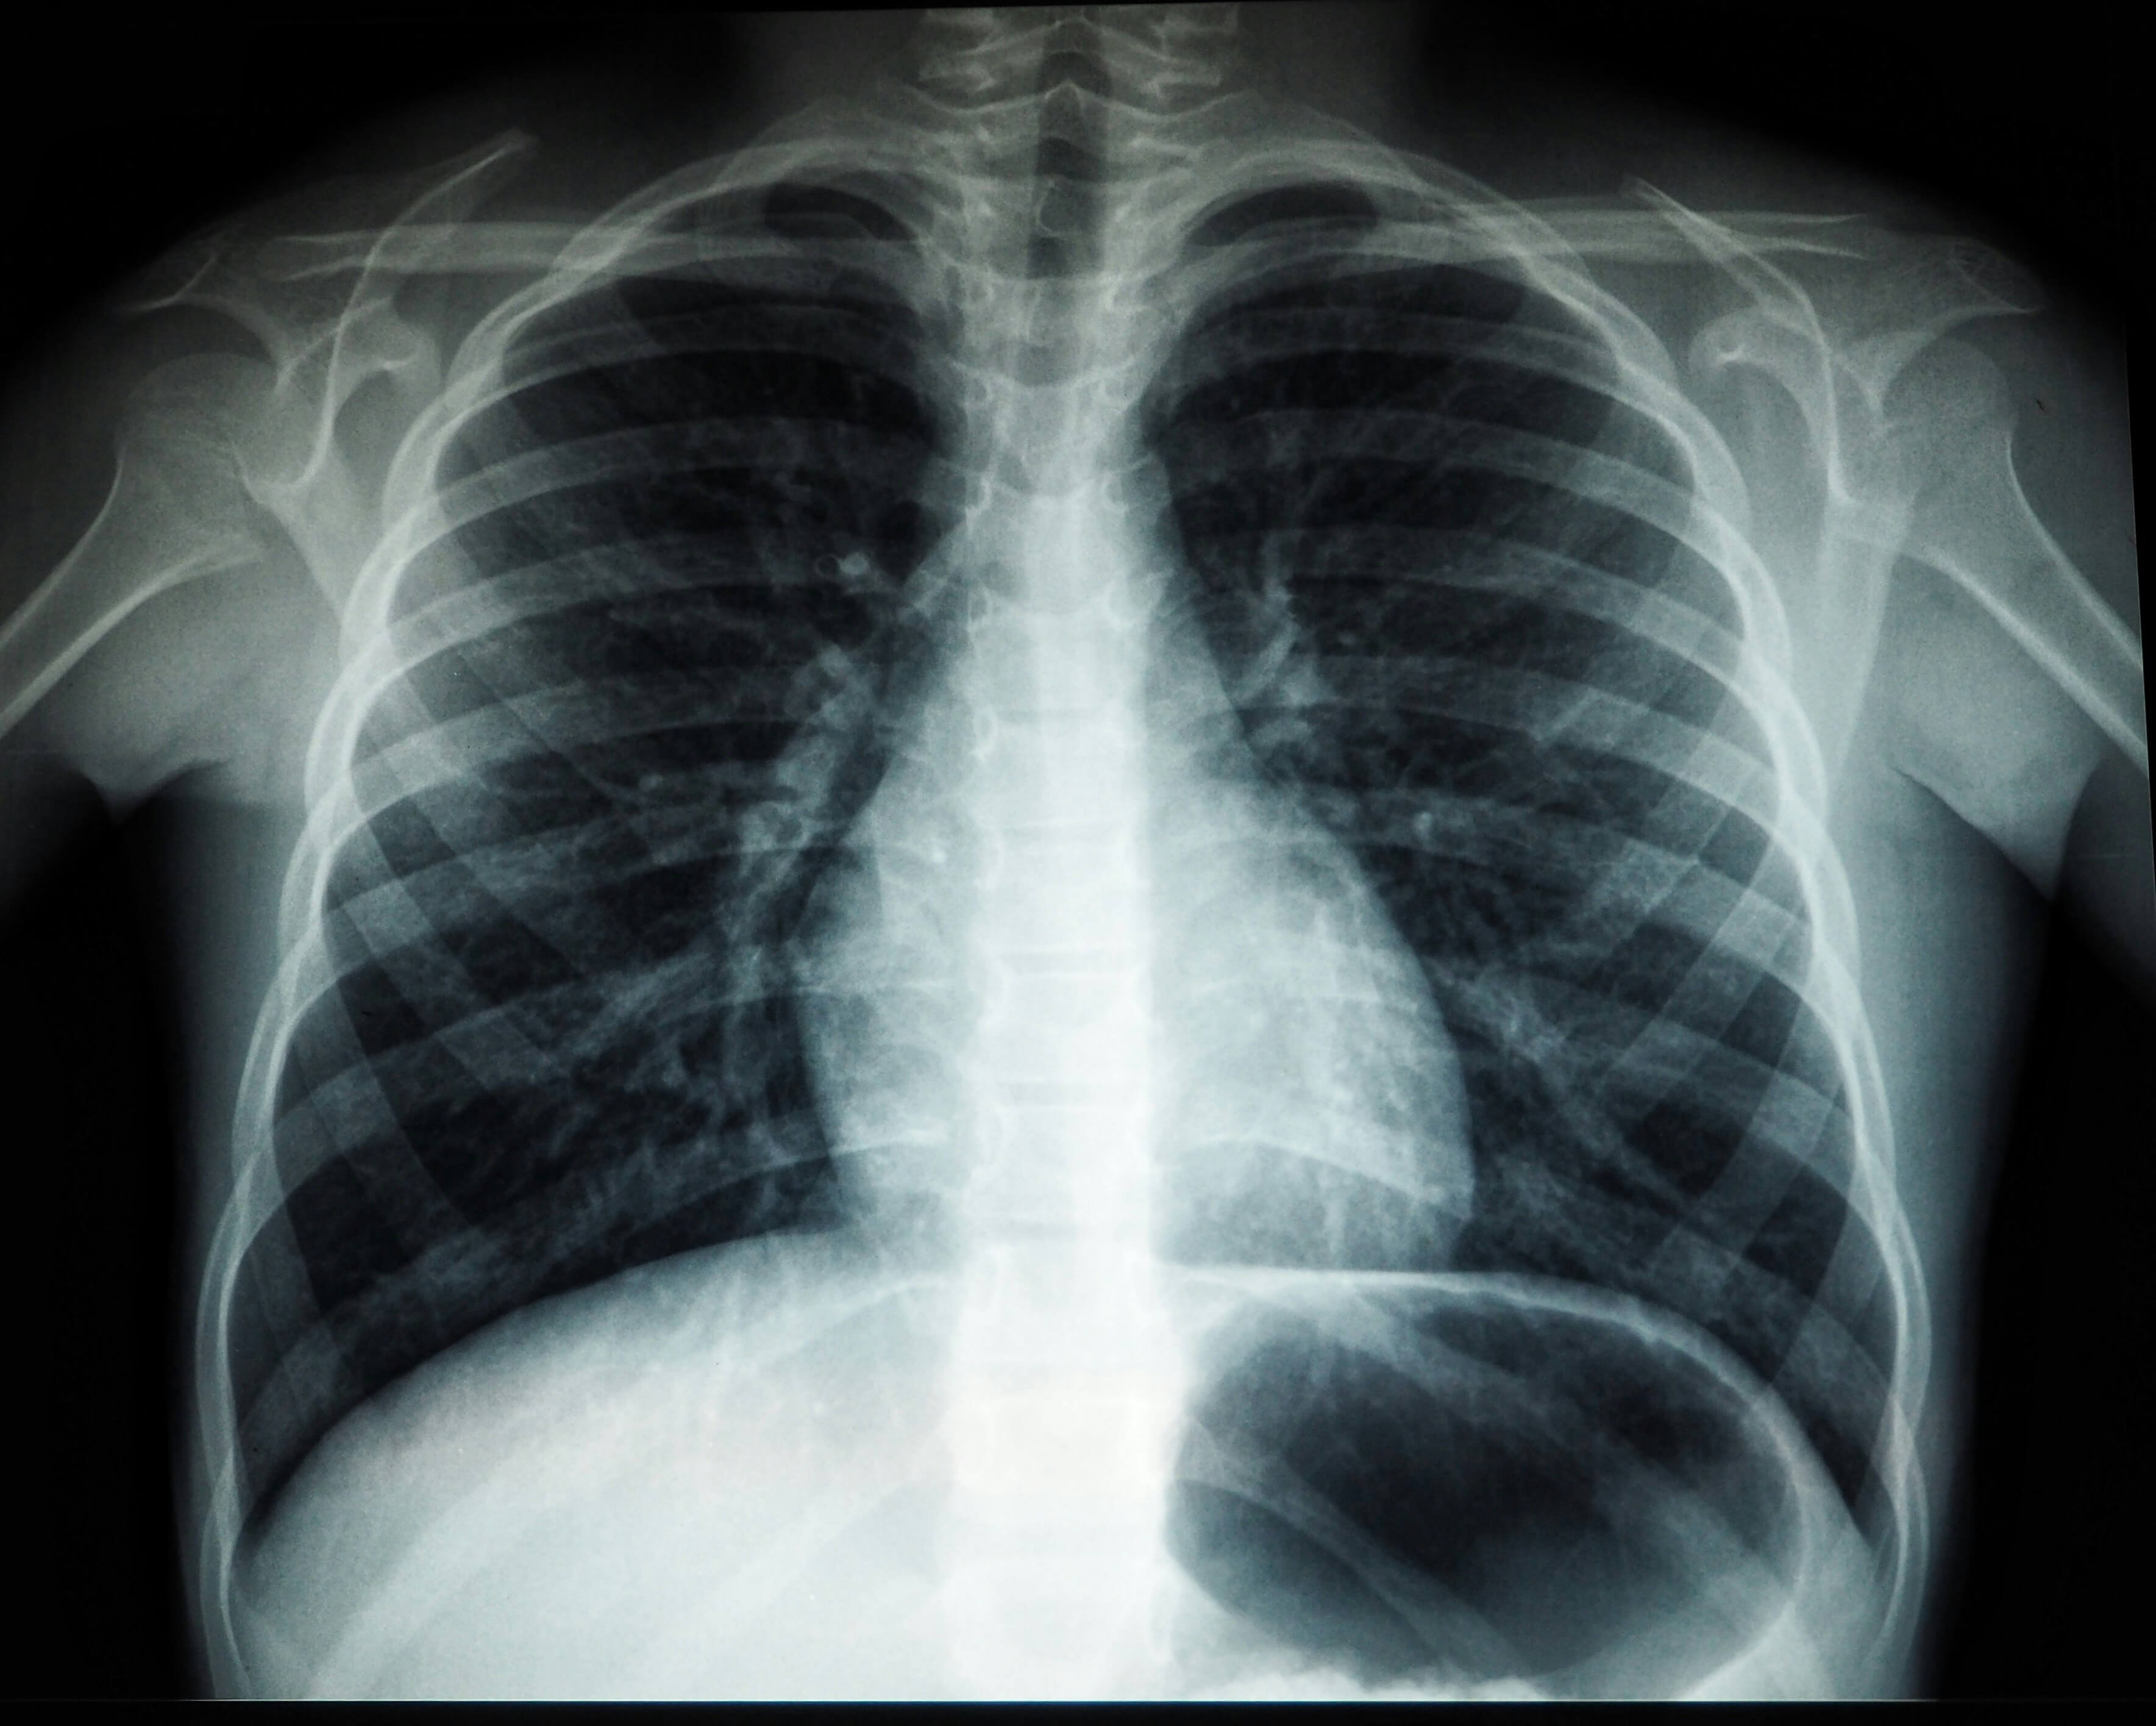

- 가슴 X선 촬영

- 가장 기본적인 진단 방법

- 폐 허탈 정도 확인